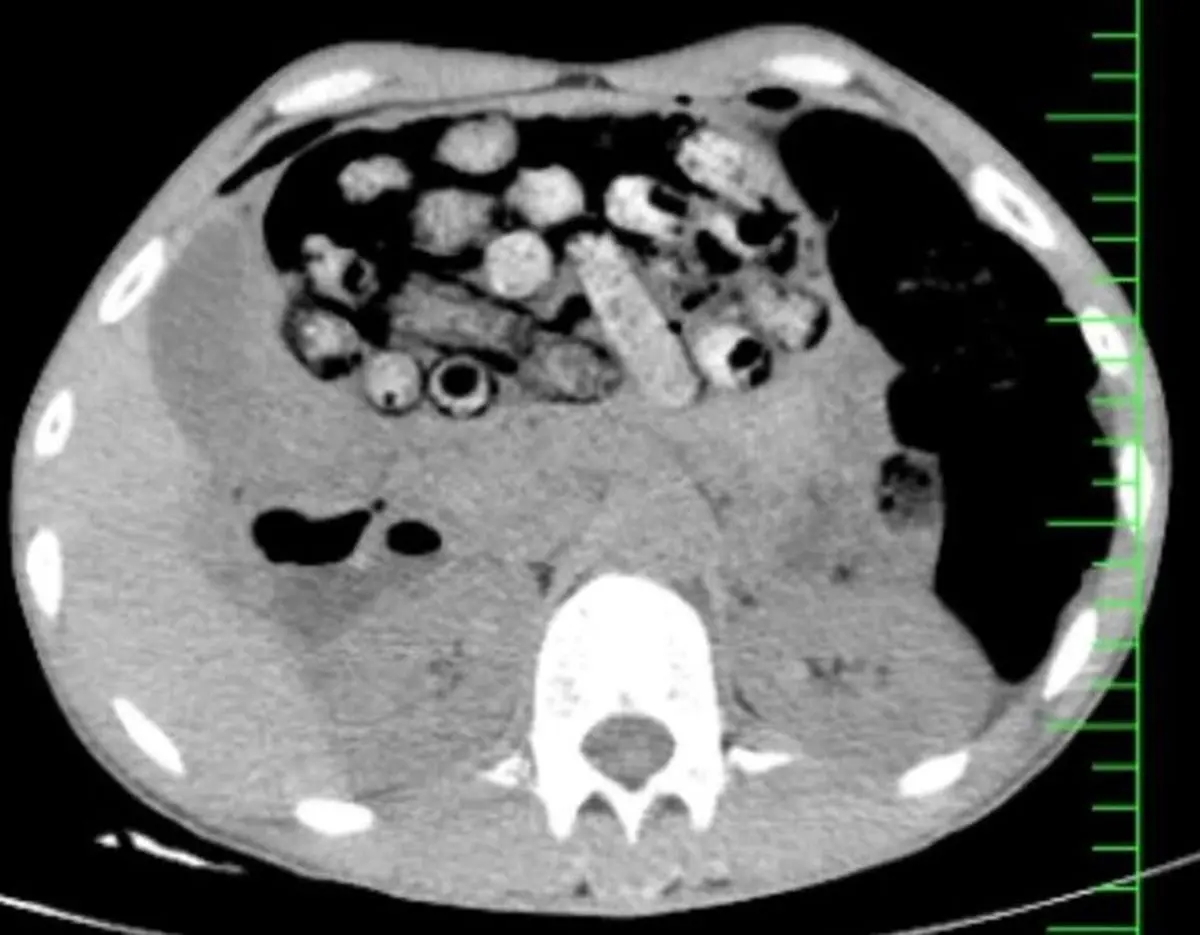

‌براساس اطلاعات اولیه مأمور همراه، بیمار پیش از مراجعه، اقدام به بلع تعدادی بسته محتوی مواد مخدر کرده بود. در پی انجام تصویربرداری فوری، تعداد زیادی بسته مشکوک در معده و روده کوچک و بزرگ وی مشاهده شد.

‌با توجه به خطر بالای پارگی احتمالی بسته‌ها و بروز عوارض تهدیدکننده حیات، بیمار بلافاصله به اتاق عمل منتقل شد و جراحی سنگین وی از ساعت سه بامداد آغاز شد.

‌در این جراحی که به سرپرستی دکتر سامان شیخی، عضو هیأت علمی گروه جراحی عمومی دانشگاه علوم پزشکی البرز و با همکاری تیم‌های اورژانس، تصویربرداری، بیهوشی و جراحی انجام و ۹۰ بسته از معده و روده بیمار خارج شد.